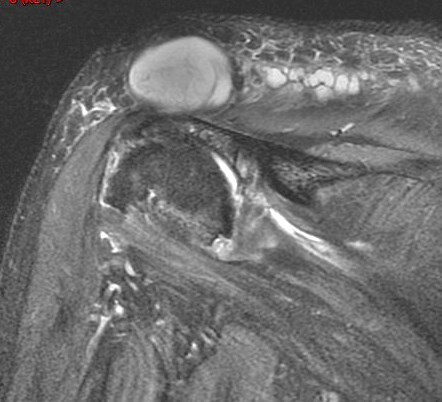

Figure 4 for case Geyser phenomenon

Figure 4

Large cyst arising from the AC joint in the setting of a chronic rotator cuff tear. Reference article.

Geyser phenomenon